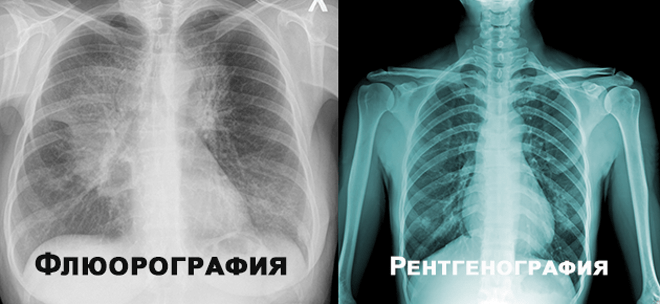

Рентген і флюорографія: різниця

Різниця між рентгеном і флюорографією — у меті використання та деталізації. Коли збираєтеся на обстеження, знайте:

- Різниця в точності: рентген робить більш деталізовані знімки.

| Розмір зображення | Повнорозмірне | Мініатюризоване |